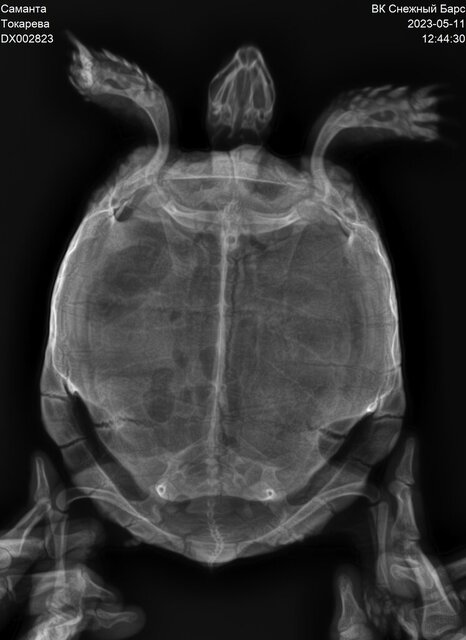

Среднеазиатская , самка, предположительно 10-15 лет

Вес 1 кг, около 20 см

Розовых пятен стало больше, пропали белые выделения. Есть биохимия крови и рентген на руках. Пожалуйста, скажите какая у нас сейчас ситуация

Ситуация следующая : нам назначили регулярные продолжительные теплые ванны. Если до конца месяца выделения не появятся, то поедем на промывание мочевого пузыря. Если после данной манипуляции не будет положительной динамики, то назначат операцию на мочевом в виду возможных нерентгенконтрастных камней.

@Дина_ меня смутил то что показатель ЩФ достаточно высокий (662) , Мочевая кислота 272

Остальные показатели низкие

Нам же сказали что это показатели в норме

Анализы и рентген на руках. Мне бы узнать какие прогнозы в действительности